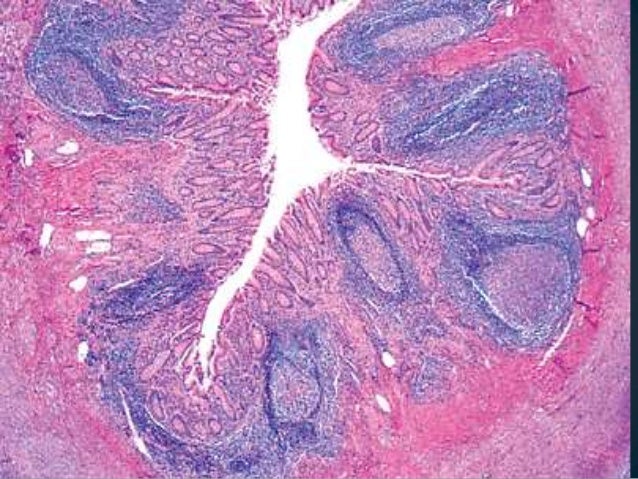

Гистология флегмонозного холецистита: изображения и примеры